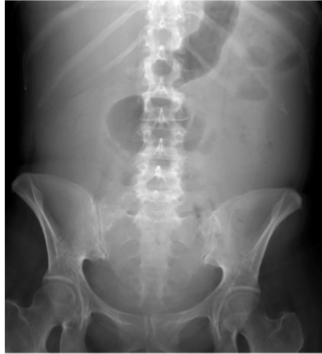

What is this and what type of scan

sigmoid volvulus (twisted) “bird beak sign or coffee bean sign”, abx